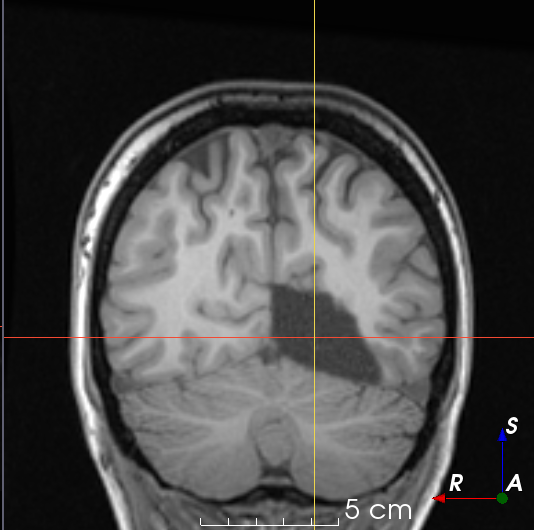

Refer to caption

(a)

(b)

(c)

(d)

(e)

(f)

Figure 3: Manual labels from Rater A (green) and Rater D, the model trained with PubFull + EpiPre + Pseudo (magenta). Errors caused by a (a) small resection, (b) blood clot in cavity and (c) brain shift; segmentations corresponding to the (d) 50th, (e) 75th and (f) 100th percentiles giving a DSC of 81.7, 86.5 and 93.8, respectively.

We trained a model using PubFull, EpiPre and Pseudo (2371 images), obtaining a DSC of 81.7 (14.2). Adding the pseudo-labels to PubFull and EpiPre did not significantly improve performance (p=0.176𝑝0.176p=0.176), indicating our semi-supervised learning approach provided no advantage. Predictions from this model are shown in Fig. 3.